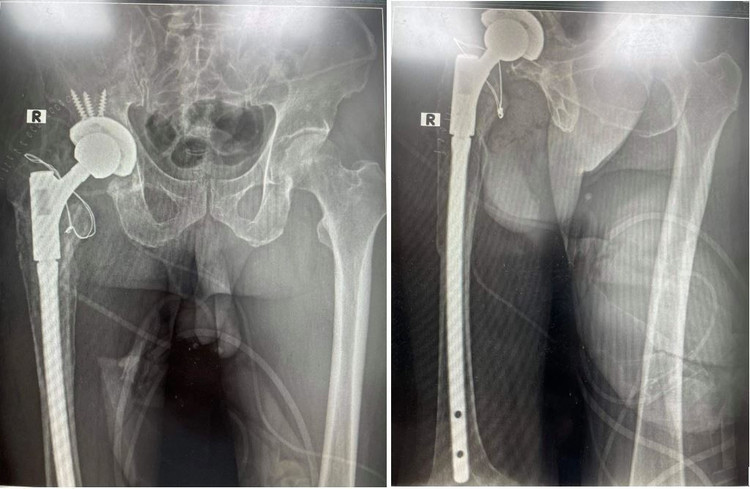

TS.BS Nguyễn Quốc Dũng, Phó Trưởng Khoa Phẫu thuật Khớp, Bệnh viện T.Ư Quân đội 108 cho biết, phương pháp điều trị duy nhất cho bệnh nhân để tránh đau đớn kéo dài là thay lại khớp háng nhân tạo. Nhưng việc thay lại vô cùng khó khăn vì hình ảnh phim X-quang và CT cho thấy khớp háng nhân tạo đã lỏng, ổ cối khuyết xương rộng và rỗng, đầu trung tâm xương đùi cũng bị xi măng ăn rỗng, chuôi khớp lún sâu vào ống tủy và nguy cơ gây thủng thân xương đùi...

Hinh ảnh phim chụp của bệnh nhân trước phẫu thuật.